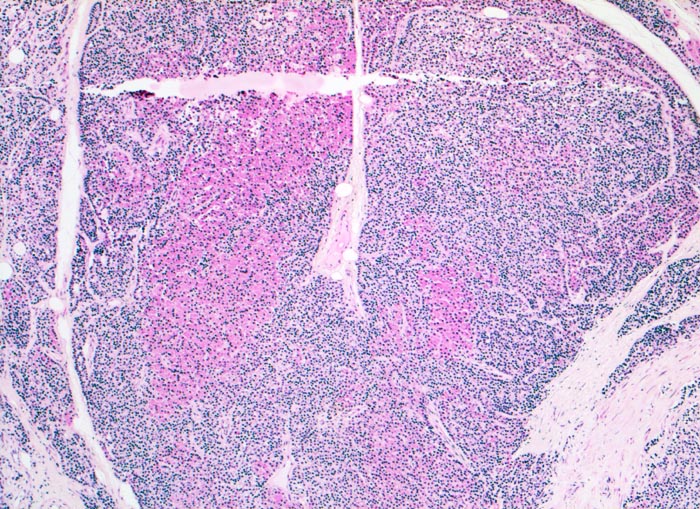

Morphologie der Nebenschilddrüsenhyperplasie:

Morphologisch besteht bei sHPT eine Hauptzellhyperplasie. Makroskopisch findet sich eine meist ungleich ausgebildete Vergrösserung aller Nebenschilddrüsen. Die Grösse der Drüsen entspricht der Schwere und der Dauer des Stimulus. Die im früheren Stadium gefundene diffuse Hyperplasie mit Ersatz des Stromas und der Fettzellen durch chronisch stimulierte Hauptzellen (> 558) (> 559) geht im späteren Stadium in eine noduläre Hyperplasie („Pseudoadenome“) über (> 2358). Die regulierte Anpassung der Nebenschilddrüsen kann in eine Autonomie übergehen (tHPT) (> 3704). Morphologisch besteht in diesem Fall eine unregelmässige noduläre Hyperplasie. Gelegentlich entwickelt sich beim tHPT ein dominanter Knoten, der morphologisch nicht von einem Adenom bei pHPT unterscheidbar ist.

Morphologische Merkmale:

• Knotige vergrösserte Nebenschilddrüse. Abgrenzung der einzelnen Knoten durch breite Fibrosebänder.

• Hyperplasie lipidarmer Hauptzellen.

• Areale mit oxyphilen Zellen.

• Verminderter Fettgehalt (<<35%). Für normale Nebenschilddrüsen gilt: